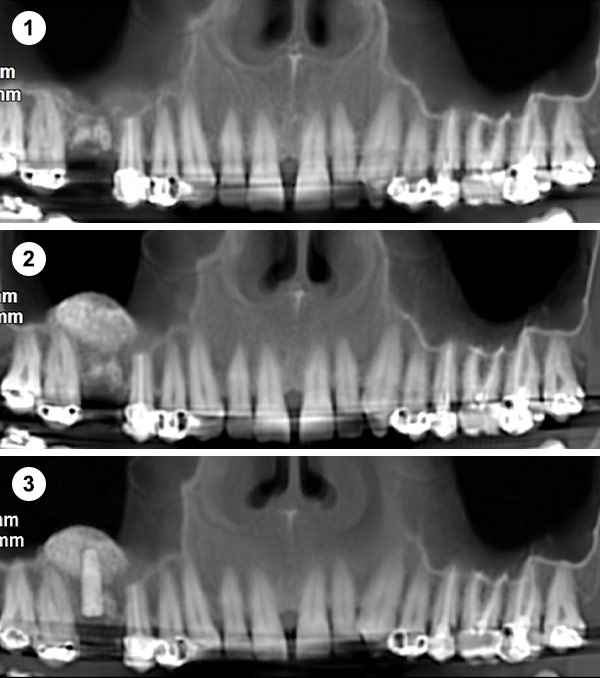

Esta técnica consiste en aumentar la altura y anchura del hueso en los maxilares introduciéndonos en el seno para conseguir una base ósea que permita la colocación de implantes.

Es un procedimiento sencillo que se realiza con anestesia local. Se practica una pequeña incisión a la altura de las raíces de los molares y premolares del maxilar superior, se crea una ventana en el hueso para acceder a la cavidad sinusal y se eleva la membrana para colocar un injerto de hueso en el suelo del seno maxilar.

Se coloca una membrana y un injerto de hueso liofilizado, un compuesto de procedencia bovina que actúa como osteoinductor (Bio-Oss), así una vez colocado induce al hueso a formar nuevas células. Lo que se intenta hoy en día es encontrar una buena calidad de injerto para acortar el período de formación de hueso. También se coloca una membrana sobre este injerto.

Se realiza a través de una apertura lateral en la pared del seno maxilar (ventana lateral). Este enfoque permite un acceso directo a la membrana sinusal para su elevación.

Indicaciones: Se emplea en casos donde la cantidad de hueso residual es muy escasa (<5 mm) o cuando se necesita un aumento significativo del volumen óseo.

Permite una visualización directa y control del procedimiento. Útil para grandes reconstrucciones óseas.